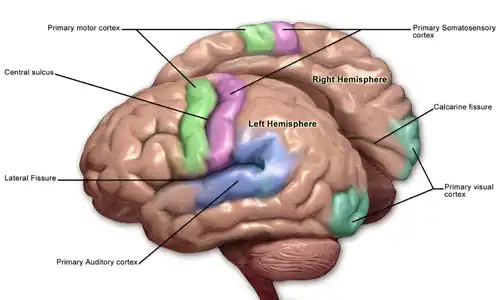

Primary somatosensory cortex labeled in purple | |

In neuroanatomy, the primary somatosensory cortex is located in the postcentral gyrus of the brain's parietal lobe, and is part of the somatosensory system. It was initially defined from surface stimulation studies of Wilder Penfield, and parallel surface potential studies of Bard, Woolsey, and Marshall. Although initially defined to be roughly the same as Brodmann areas 3, 1 and 2, more recent work by Kaas has suggested that for homogeny with other sensory fields only area 3 should be referred to as "primary somatosensory cortex", as it receives the bulk of the thalamocortical projections from the sensory input fields.[1]

At the primary somatosensory cortex, tactile representation is orderly arranged (in an inverted fashion) from the toe (at the top of the cerebral hemisphere) to mouth (at the bottom). However, some body parts may be controlled by partially overlapping regions of cortex. Each cerebral hemisphere of the primary somatosensory cortex only contains a tactile representation of the opposite (contralateral) side of the body. The amount of primary somatosensory cortex devoted to a body part is not proportional to the absolute size of the body surface, but, instead, to the relative density of cutaneous tactile receptors located on that body part. The density of cutaneous tactile receptors on a body part is generally indicative of the degree of sensitivity of tactile stimulation experienced at said body part. For this reason, the human lips and hands have a larger representation than other body parts.